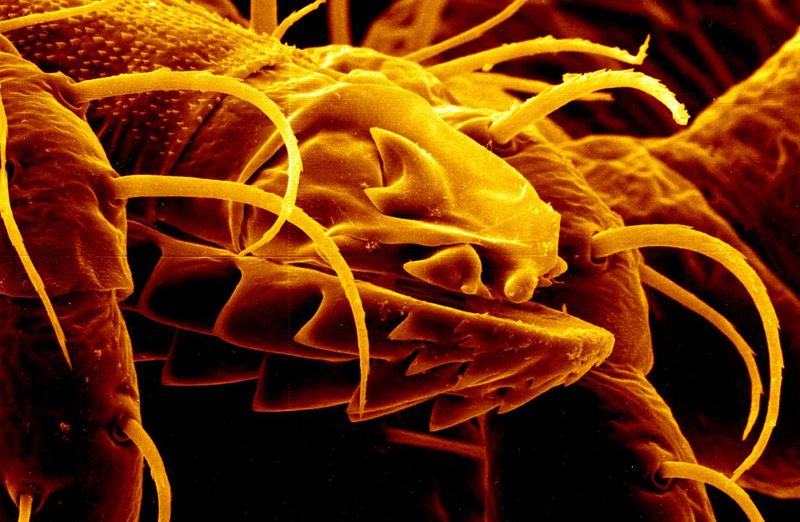

To go about this, the researchers developed the ‘long-term embryo culture device’. The device involves a complex system of fluid containers, where the embryo develops, aided by a series of fluid controllers and supplemented by oxygen. Above the cultures is an optical device capable of magnifying the embryos and monitoring them with impressive detail, which provides key growth information to the AI nanny. Based on this information, the AI can even rank the embryos on overall health and potential, should the researchers wish it.